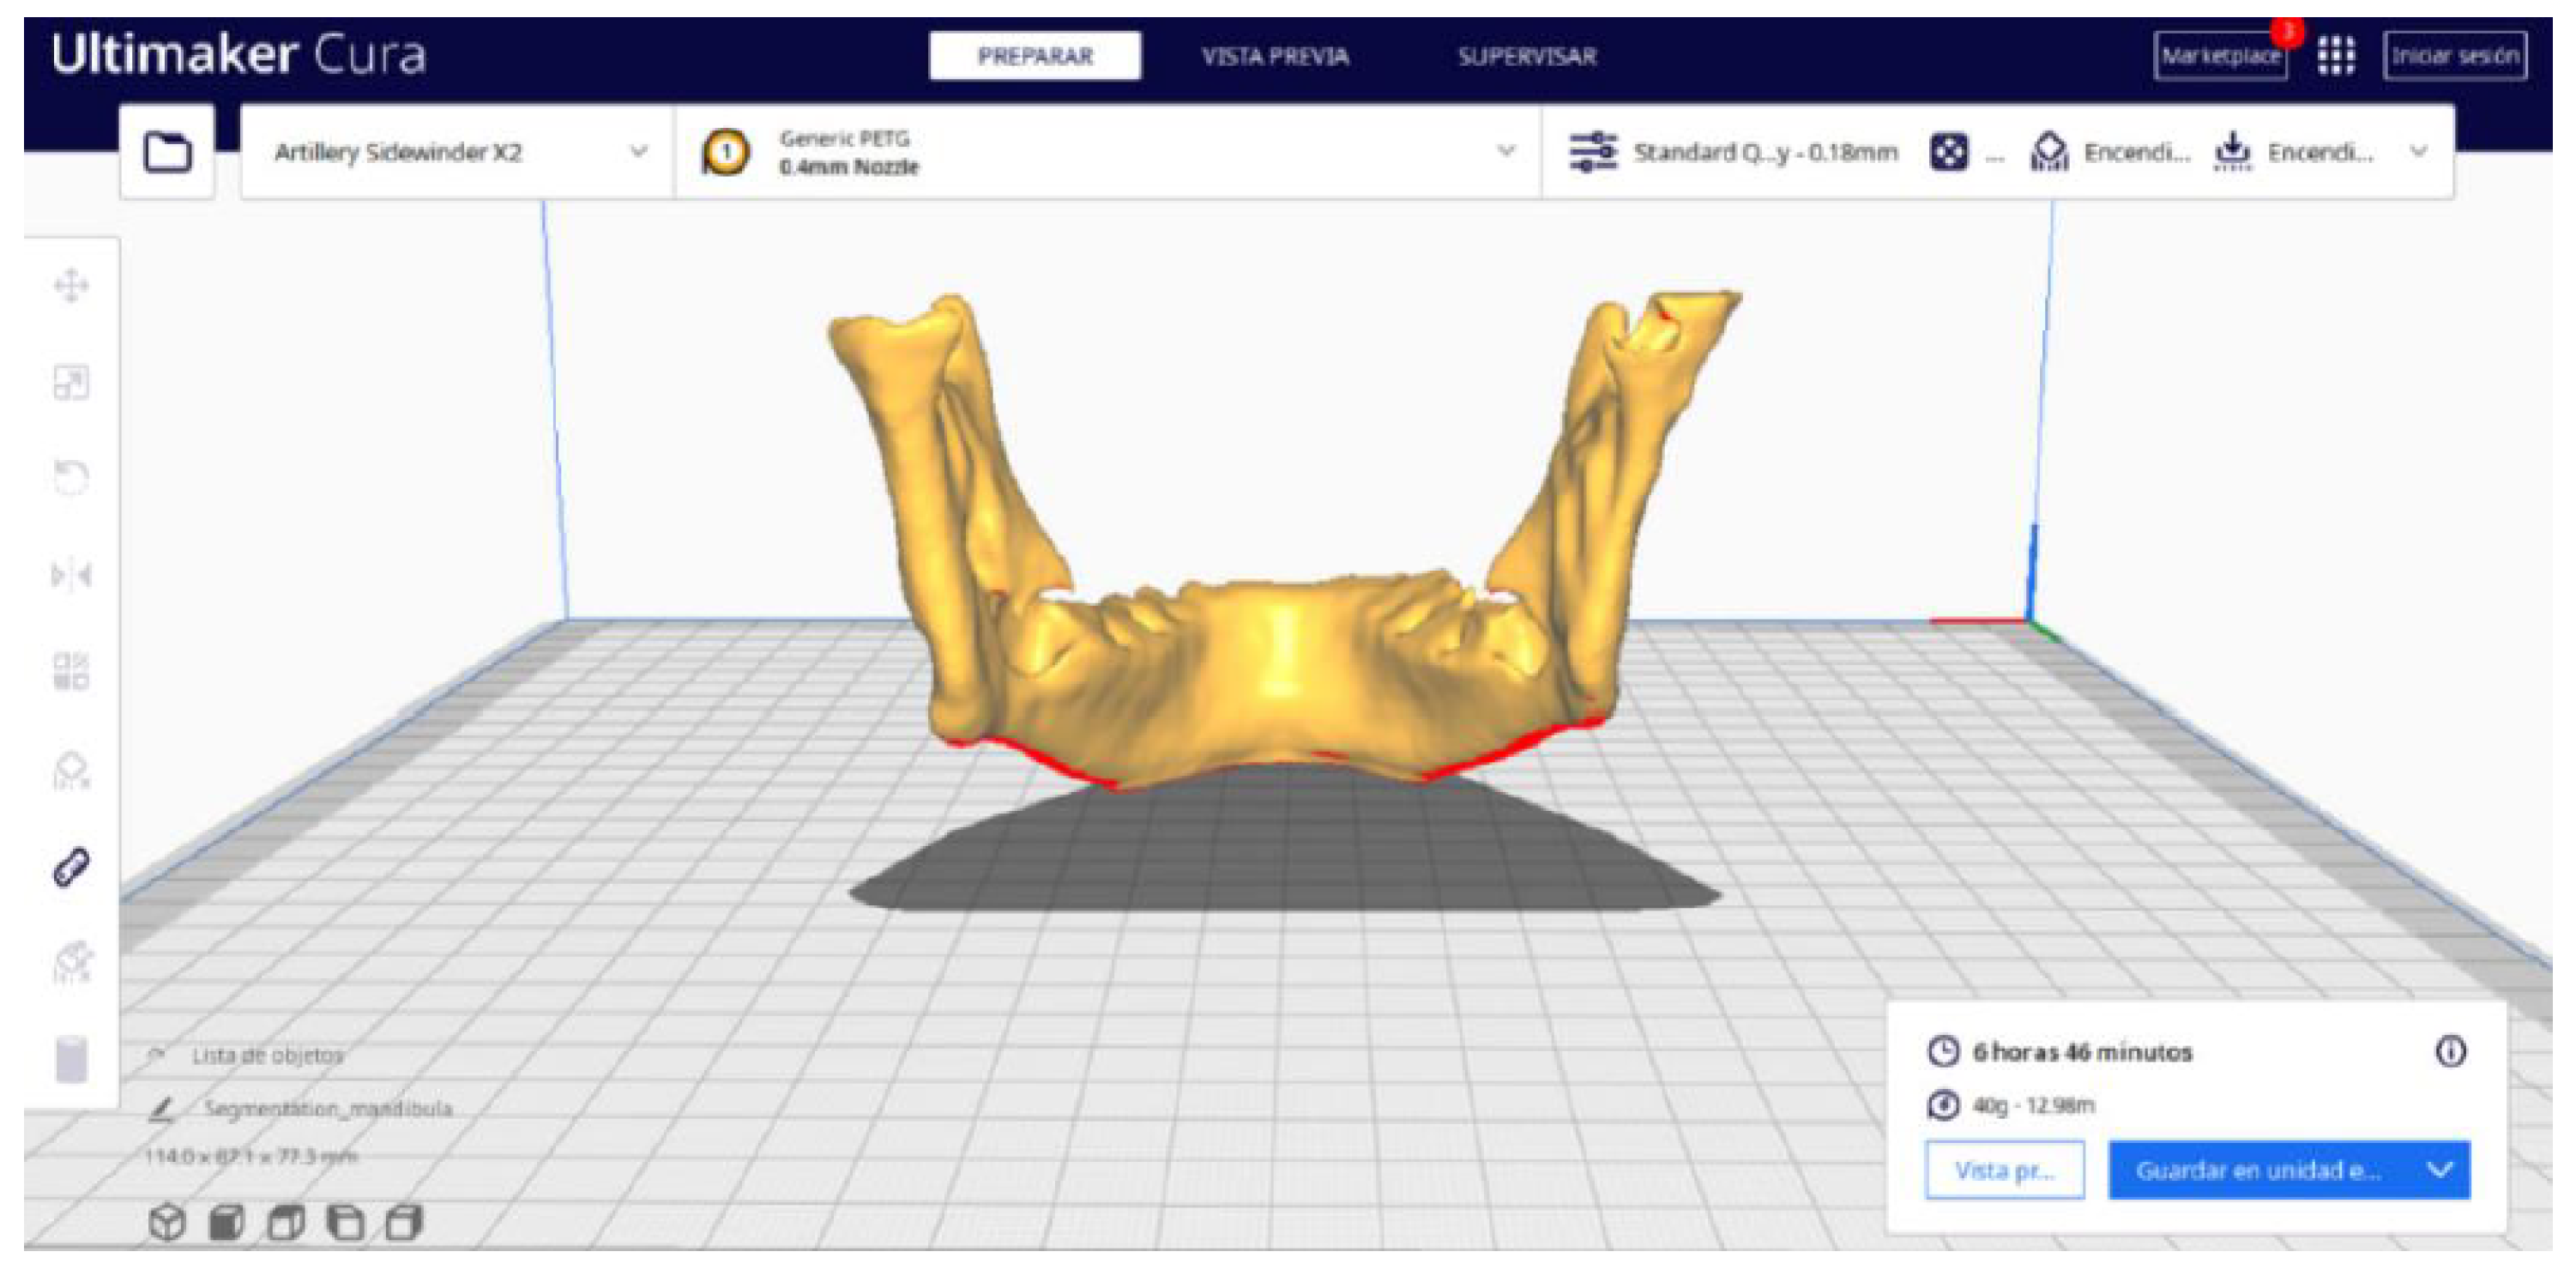

2.2. STL-to-GCODE File Conversion

- Launch the Ultimaker Cura program on your computer.

- Open the STL file you want to print from the “Open File” option in the menu.

- Access the printer settings within Ultimaker Cura.

- Be sure to select the appropriate printer model and material settings for your 3D printer.

- If necessary, make adjustments to the position, scale, or rotation of the model on the build platform within Ultimaker Cura. This allows you to optimise the layout of the model on the printing platform.

- Choose the appropriate support structure type and pattern to ensure the successful printing of complex geometries, adjusting the adhesion to the build plate as necessary.

- Select an adhesion type to improve the first coat’s adhesion to the build plate, reducing problems associated with poor first coat adhesion.

- In order to continue the STL file to GCODE conversion process, select the “Segmentation” option in Ultimaker Cura.

- The segmentation tool provides valuable information such as the estimated model weight and estimated printing time, among other crucial data.

3.2. Human Lower Jaw

3.2.2. STL-to-GCODE Files